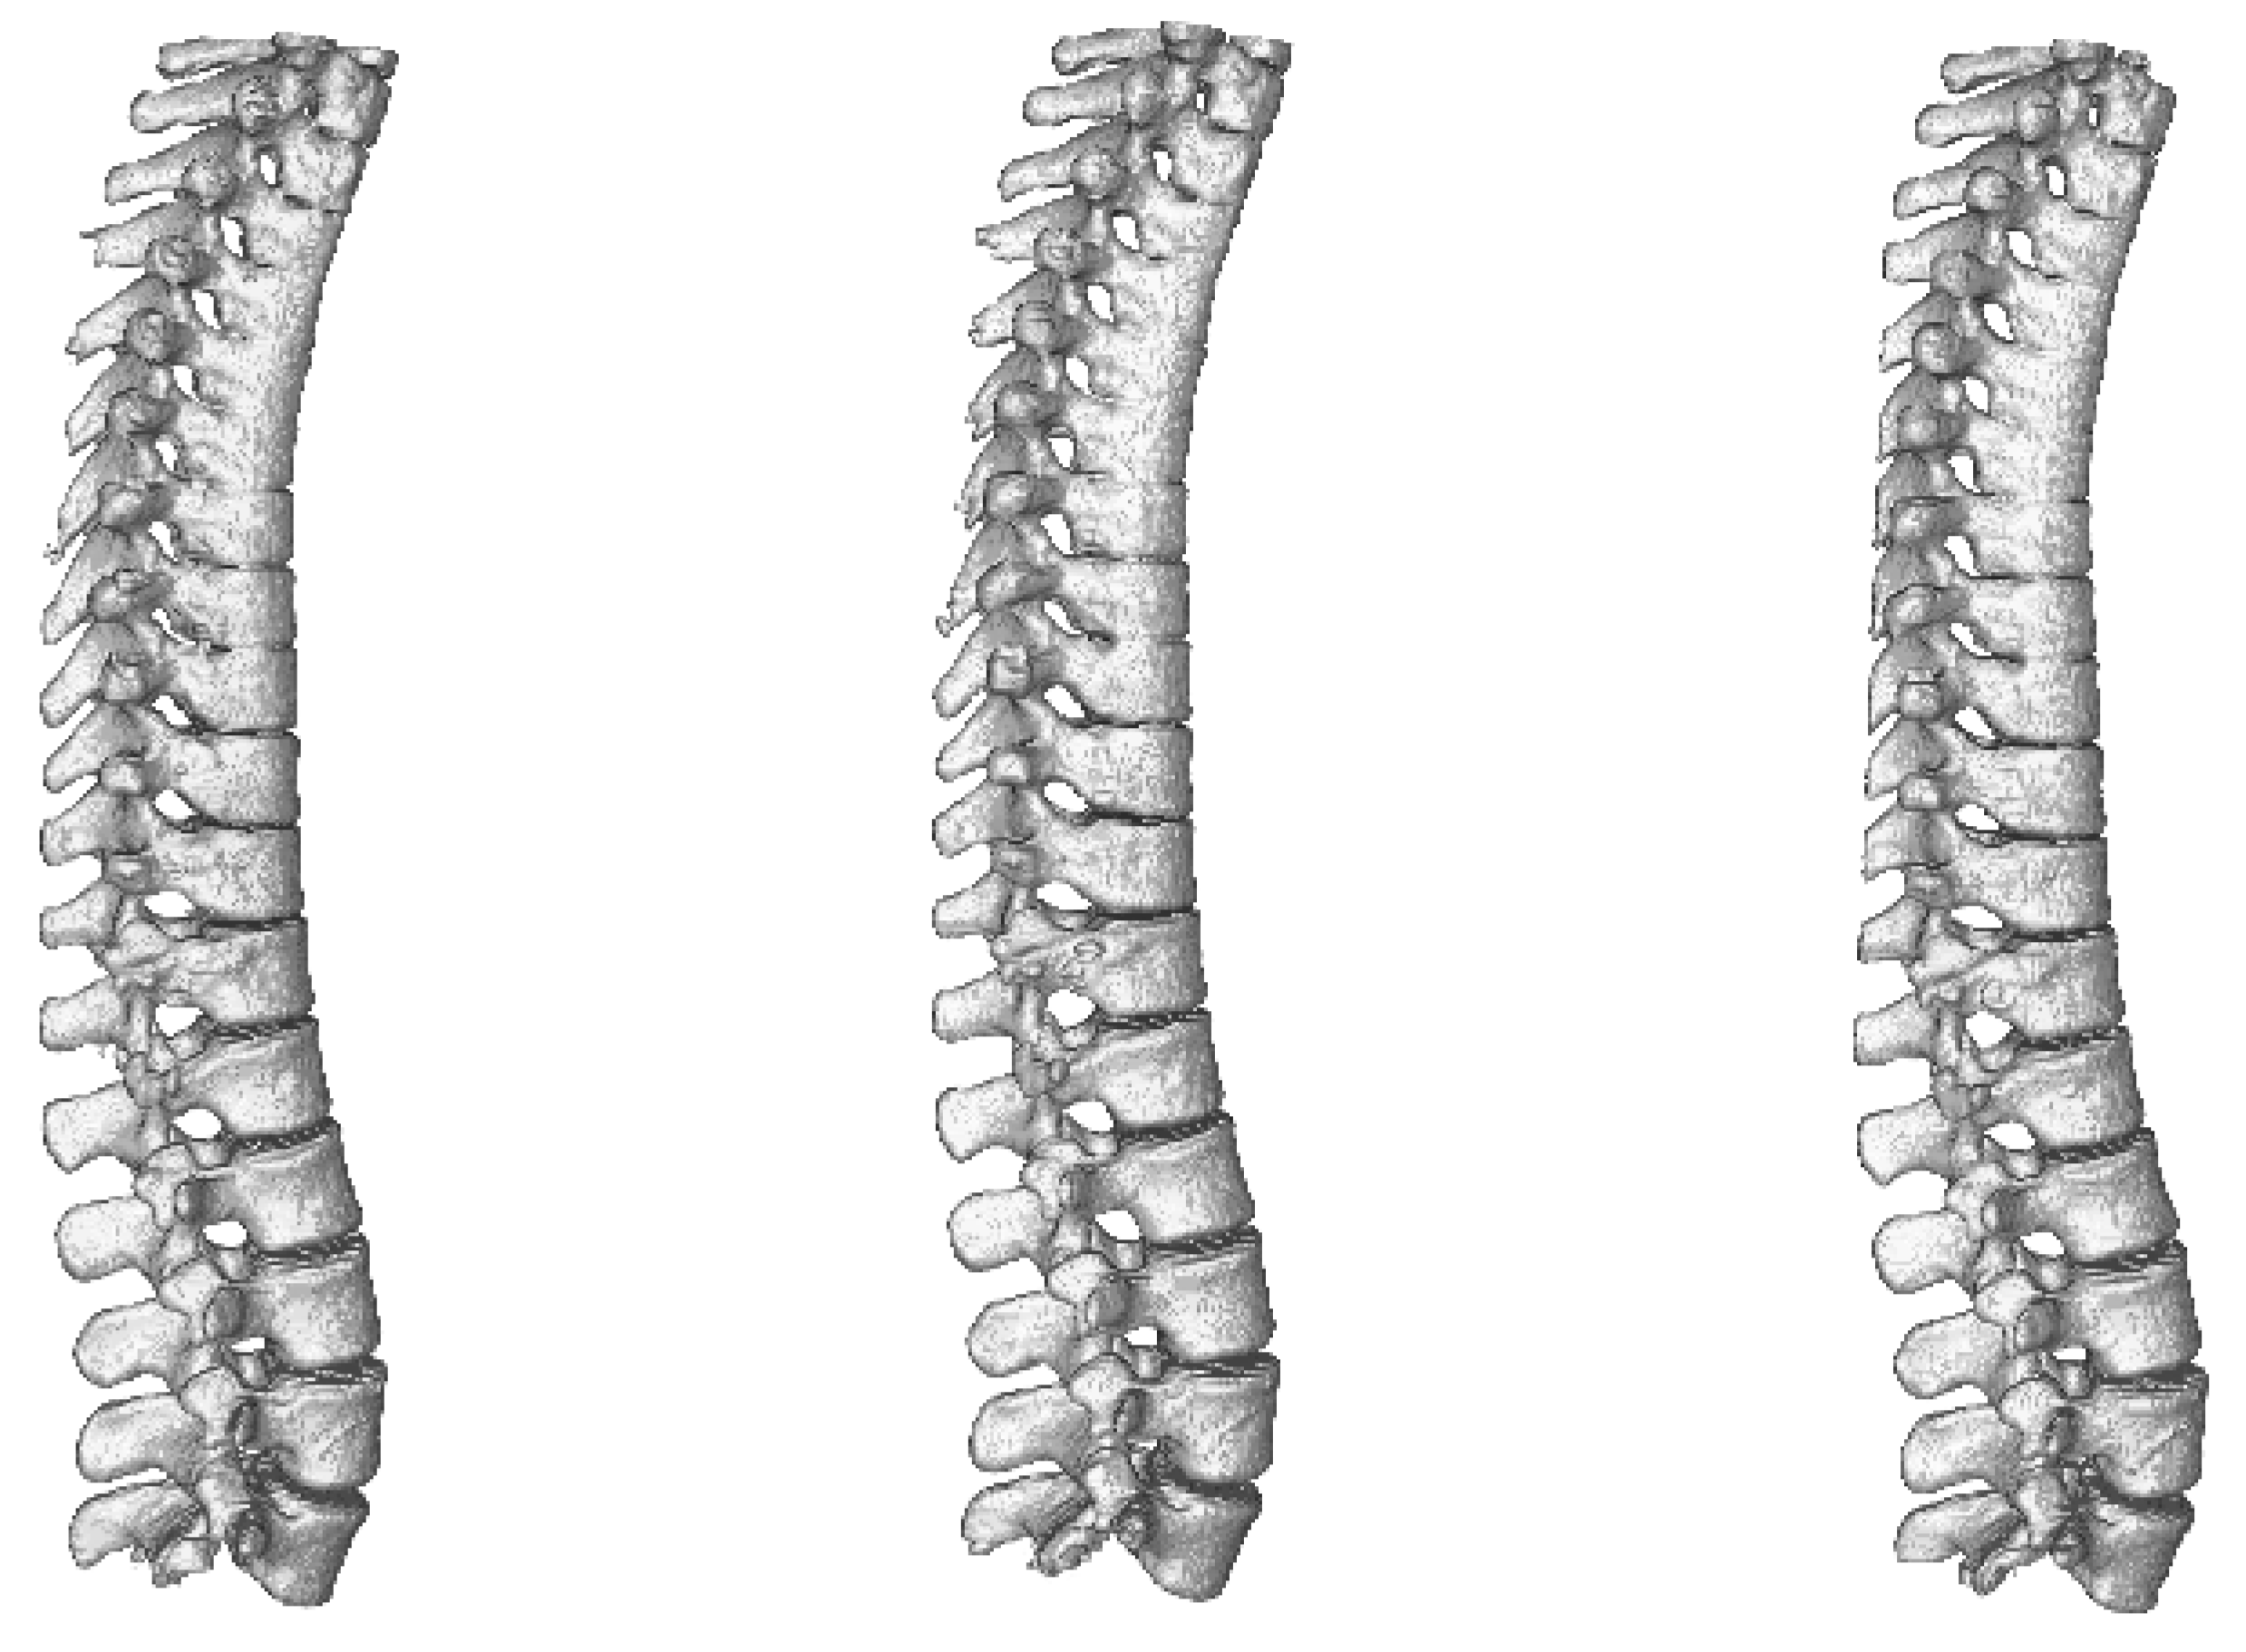

As the benchmark comparison of tested architectures in 2D vs. 3D versions is done on brain dataset, we trained and evaluated only 3D versions of the networks. A comparison of results achieved during benchmark phase using all three architectures can be seen in Table 6 and visualisation of the segmented spine models can be seen in Figure 9. This dataset does not contain second set of labels done by a human expert and therefore the results cannot be compared with human precision.

Figure 9.

Visualisation of segmented spine models from the benchmark training phase. From left to right—Dense-U-Net, Residual-U-Net, U-Net. Please notice that the abnormal vertebrae adhesions exist also in original ground truth masks as can be seen in Figure 10.

Dense-U-Net network has achieved the highest results in all metrics except for average Hausdorff distance. Reason for this is that the model does not perform well on borders of the image. In the dataset there were labelled only thoracic and lumbar vertebrae, but the CT scans contained also the first cervical vertebra and the network did include it in its segmentation results. You can see a part of the first cervical vertebra on top of the segmented spine in Figure 10.